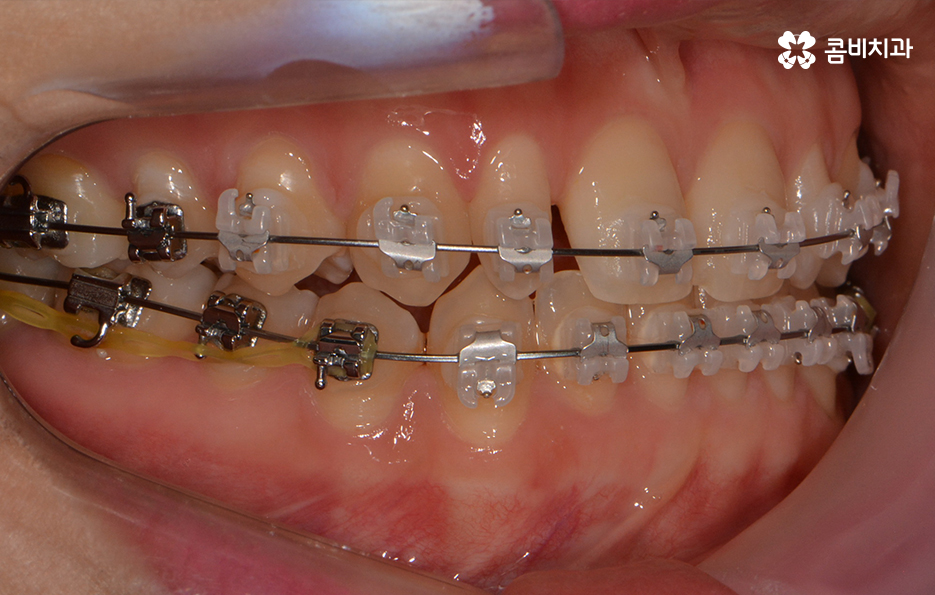

옆모습을 볼 때 치아 사이가 유독 벌어져 보이는데 심미적으로도

부담감을 느끼실 수 있지만 음식물이 치아 사이에 낀다거나

치아의 벌어짐으로 인해 치열이 반듯하게 자라지 못하기도 합니다.

전체적인 치열 상태가 비교적 가지런한 편이었기 때문에

약 1년 정도 클리피씨교정을 통해서 치열과 교합 개선이 진행 되었습니다.